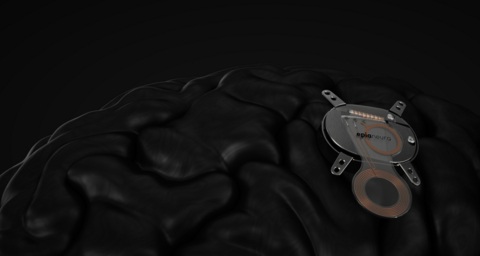

- Wearable Scanner Images the Entire Brain